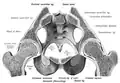

Основу таза образуют две тазовые кости, крестец и копчик, соединённые суставами пояса нижних конечностей в костное кольцо, внутри которого образуется полость, заключающая внутренние органы. До возраста 16—18 лет кости (подвздошная, лобковая и седалищная) соединены хрящами. Впоследствии происходит окостенение, и указанные кости срастаются между собой, образуя тазовую кость. Также при сращении этих костей образуется вертлужная впадина (лат. acetabulum).

Парные тазовые кости спереди соединяются при помощи лобкового симфиза, а сзади прикрепляются ушковидными поверхностями к одноимённым образованиям крестца, образуя парные крестцово-подвздошные суставы. Каждая из тазовых костей в свою очередь образована тремя составляющими: подвздошной костью, седалищной костью и лобковой костью, тела которых на наружной поверхности образуют вертлужную впадину (лат. acetabulum)— суставную ямку для головки бедренной кости, с которой образуют тазобедренный сустав.

Парные тазовые кости вместе с анатомическими образованиями, идущими от них и таза к бедренной кости и бедру, посредством которых происходит прикрепление ног к позвоночнику (крестцу), образуют тазовый пояс (пояс нижних конечностей).